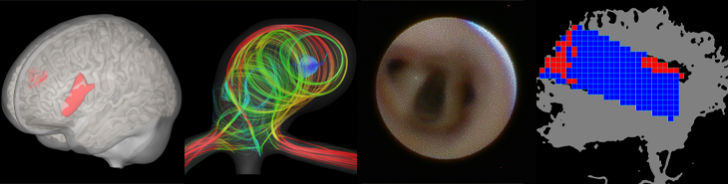

Neuroradiology is your contact partner for diagnostics and minimally invasive therapy of diseases and changes of the nervous system, i.e. of the brain and spinal cord, peripheral nerves and the immediate adjacent structures (e.g. the spine).

Diagnostically and therapeutically, the most modern methods and equipment are available for our patients. In addition to diagnostic neuroradiology, our clinic is characterized by a high level of expertise in minimally invasive neuroradiological therapy, both in the emergency treatment of strokes and in the elective treatment of aneurysms, vascular stenoses and vascular malformations.